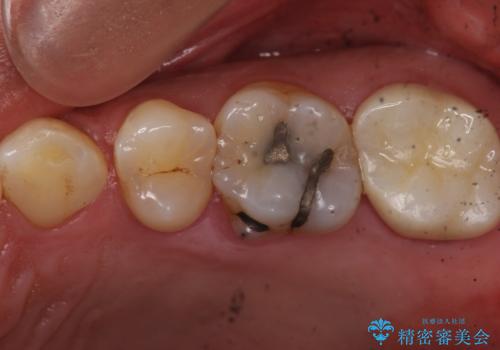

また矯正後、患者様の希望で

メタルインレーをセラミックインレーにやりかえさせていただき、さらに綺麗に仕上がりました。